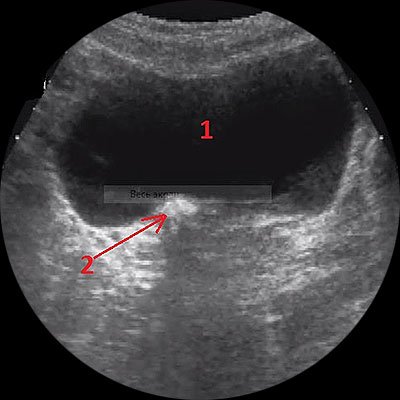

Изображения КТ конкрементов мочевого пузыря